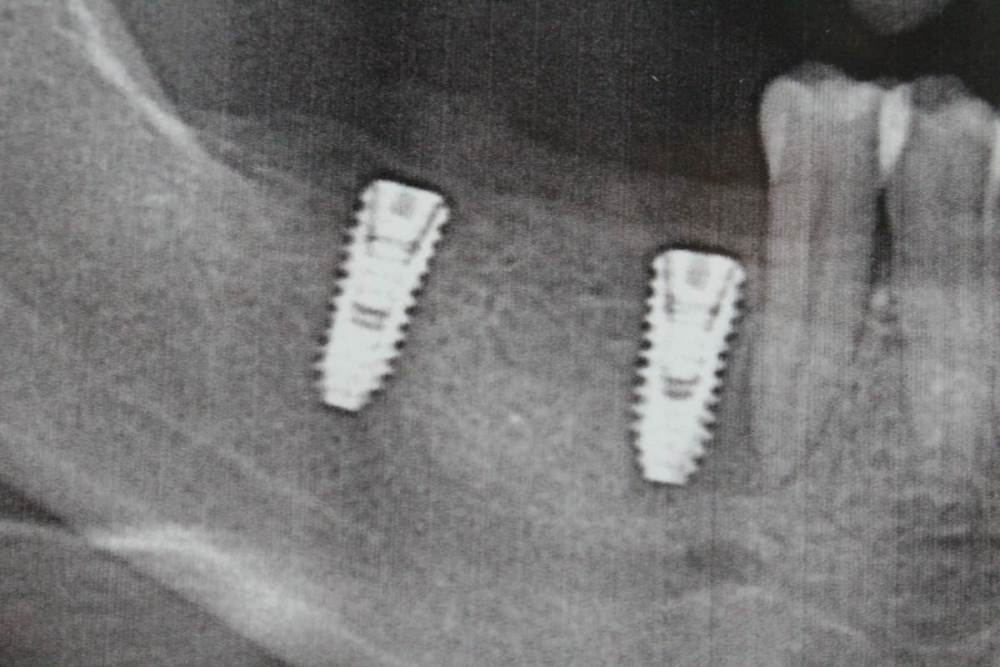

Олеся С Опубликовано 22 октября, 2021 Поделиться Опубликовано 22 октября, 2021 (изменено) Здравствуйте. Установили два импланта, нижние 6 и 7. На месте шестерки через неделю воспалилась десна, вышла шишечка на десне (со стороны щеки). Болей и температуры не было. Швы сняли, заодно промыли, выходила кровь. После промывания продолжила делать ванночки, пропила курс Азимак. Три дня все было хорошо. Снова появилась шишечка, снова прокололи, промыли. Пренеприятнейшее занятие) Сейчас второй день после промывания, воспаления сильного нет, шишечка вроде ушла, болей нет. Сделала снимок. Что там не так? Врач не сдается, сегодня раскрутил заглушку, что-то там колдовал. Мало что рассказывает. Имплант снимать не хочет, сказал ходить еще неделю. Говорит, сниму за минуту, но не надо торопиться. Стоит ли тратить время или все таки надо снимать имплант? Возможно ли, что приживется нормально? Изменено 22 октября, 2021 пользователем Олеся С Ссылка на комментарий

Irouil Опубликовано 22 октября, 2021 Поделиться Опубликовано 22 октября, 2021 Я бы рекомендовал сделать компьютерную томографию, если судить только по этому снимку то однозначную оценку дать сложно Ссылка на комментарий